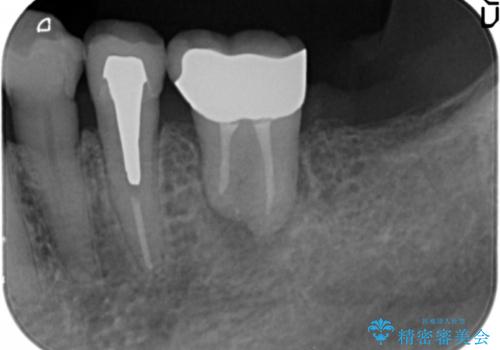

親知らずの移植 4年半経過症例 70代女性

- 親知らずの移植治療から4年半経過した患者様です。

他の歯の治療をご希望され、数年ぶりに来院して下さいました。

移植した親知らずは全く問題ないそうで、「まるで自分の歯のようです。本当にすごい技術ですね。」とおっしゃって下さいました。

歯肉の腫脹や退縮、動揺も認められませんでした。